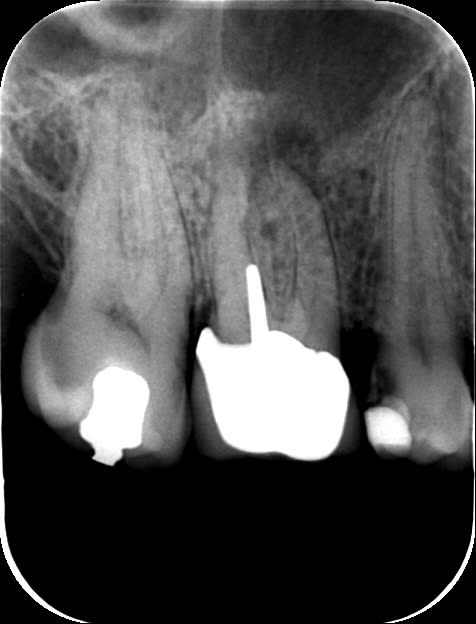

16 pasdendosousccm yl8wbi - Eugenol

Ce que je ne comprend pas c'est coller un ic coiffe sur une merde pareille. L'effet boomerang est garanti et bonjour à te faire chier et à tout déposer. Quitte à faire de la merde je t'y aurais collé un amalgame-pouce opposable screw post dentatus inside.